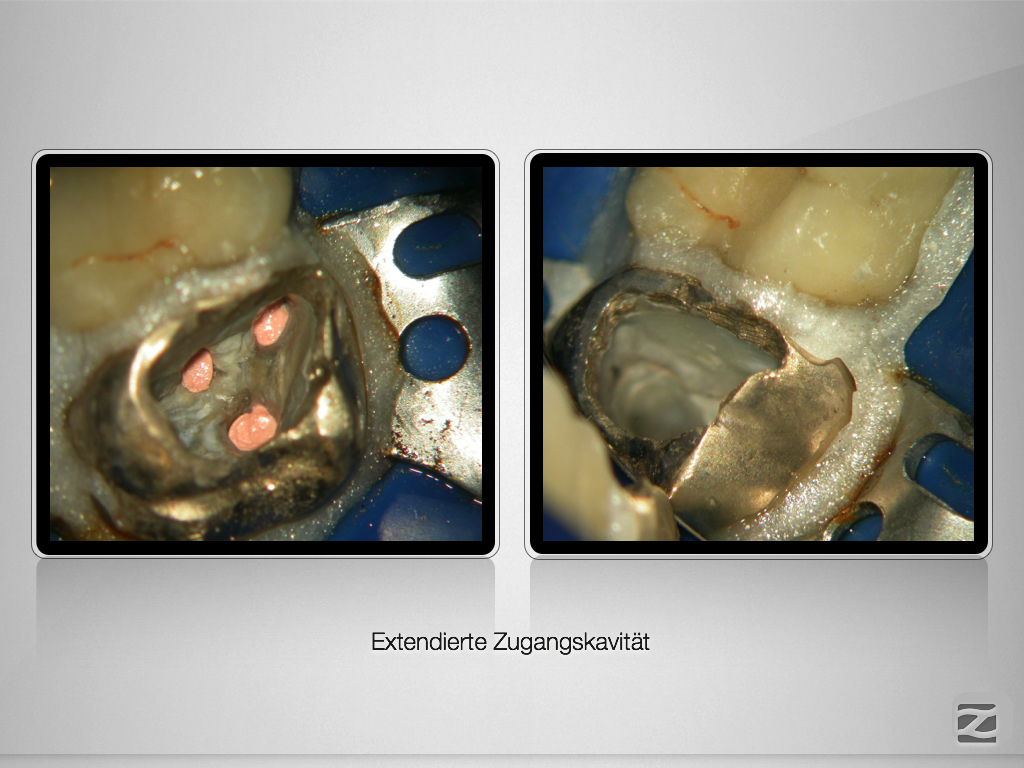

Hyflex Fallbeispiel (1/3)